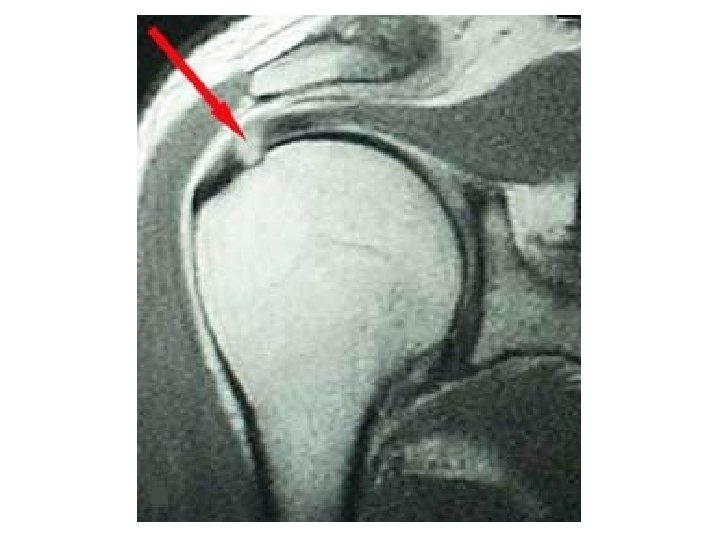

Diagnosis of RC Tear • First Step – Clinical Exam – Strength Testing • 2 nd Step – X-ray – will not show tear, but will rule out bony problem (avascular necrosis, fx, dislocation) • 3 rd Step – MRI – no need to MRI if strength is 5/5 – try conservative approach first – PT, steroid injection

Rotator Cuff Pathology Impingment Tear/Sprain